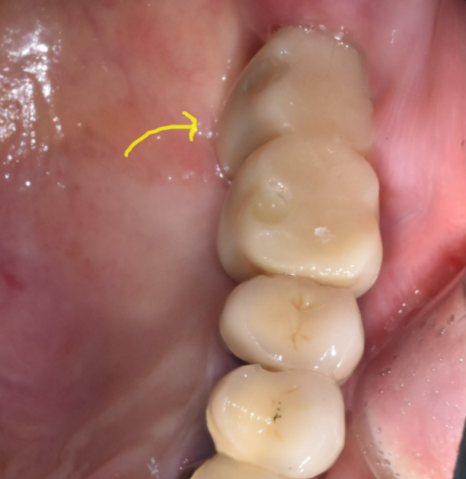

231226

수술 후 3개월 뒤 모습입니다.

임플란트 주변으로 뼈가 둘러싼 모습이 확인 된 후

잇몸을 여는 수술을 진행하였습니다 .

240227

묻어놨던 임플란트를 세상 밖으로

잇몸 위로 작은 뚜껑을 연결한뒤

잇몸이 차오르기를 기다렸는데요

240315 머리를 올리는 작업

위아래 임플란트 수술도 동시에

머리 만드는 작업도 한번에 해주었습니다.

241127

완성된 모습입니다.

뼈가 부족한 윗니 어금니로 인해

시간이 조금 걸렸습니다.

240503

머리 부분은 하얀색으로

심미적이게 제작 완료!